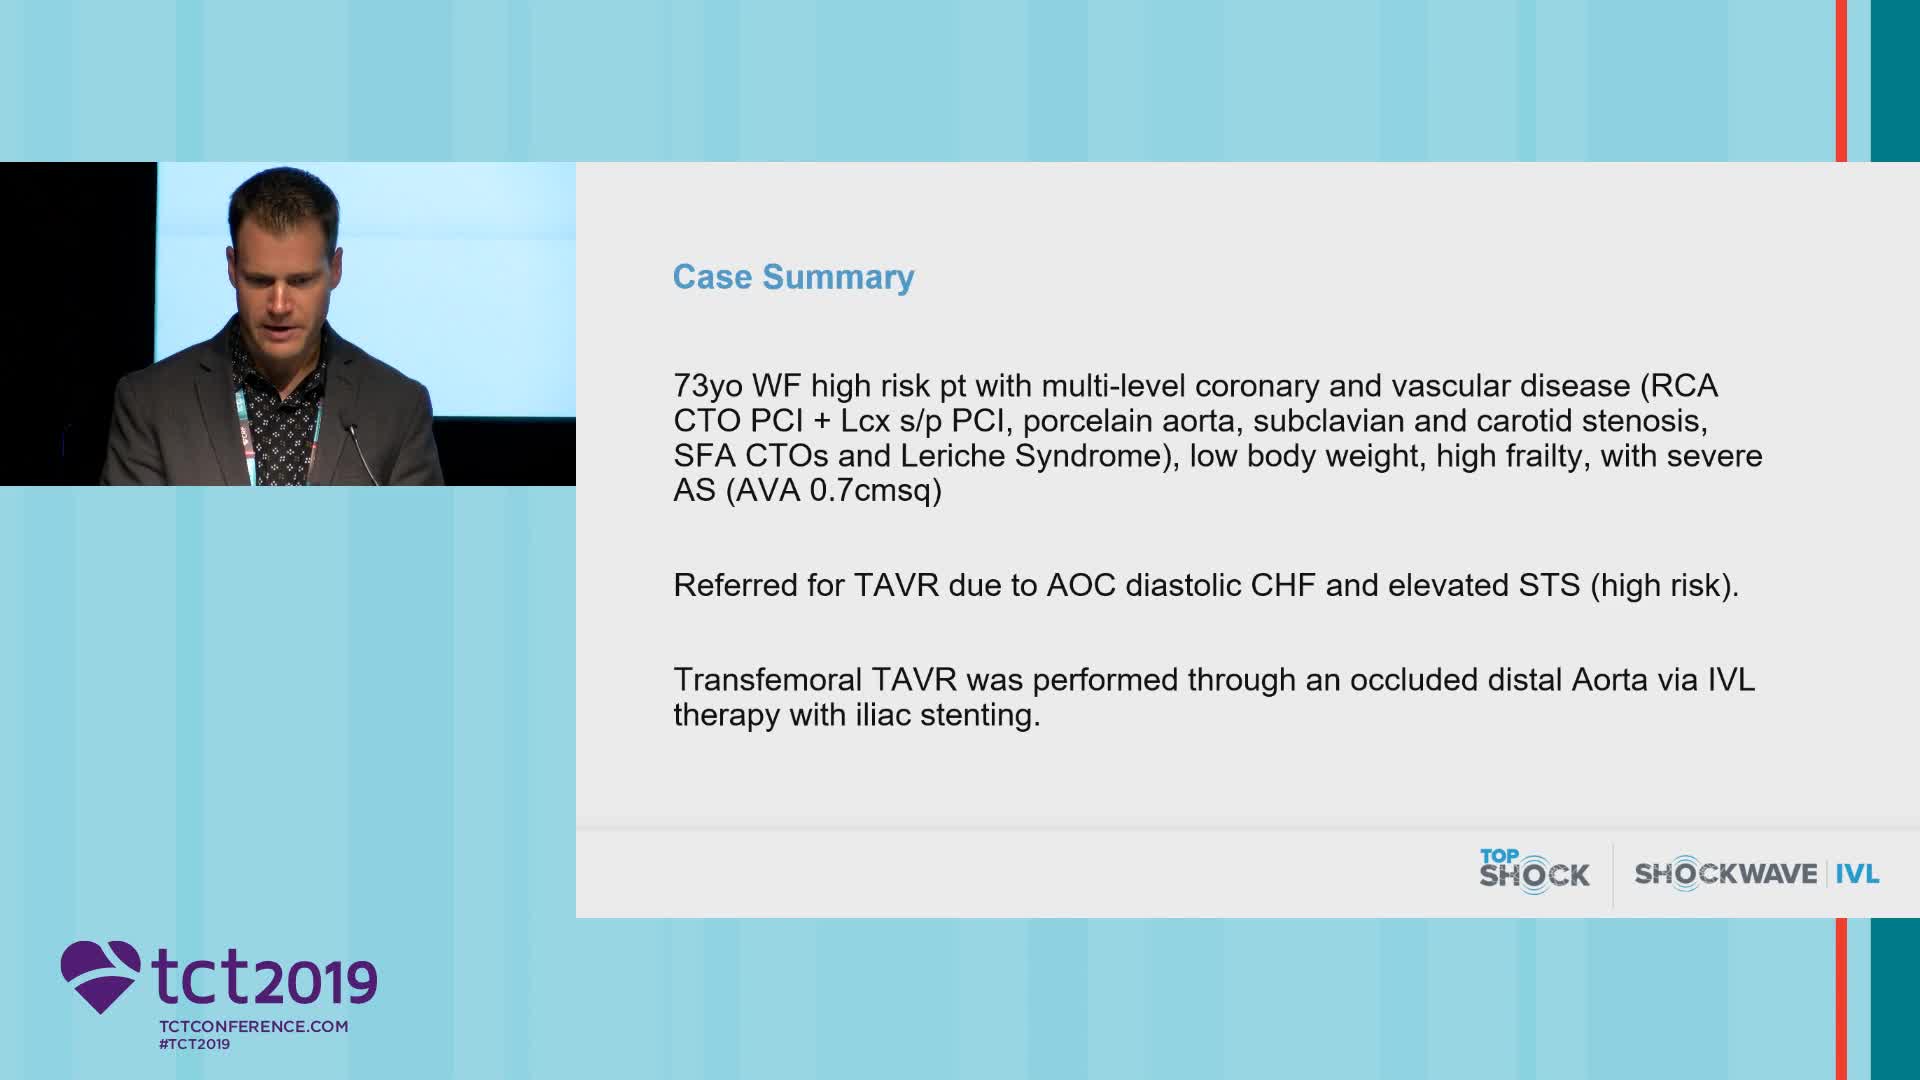

IVL to facilitate Transfemoral TAVI

Simplify your procedures with Intravascular Lithotripsy (IVL) by safely modifying intimal and medial calcium to achieve optimal outcomes while minimising trauma, complications and costs due to its unique MOA.